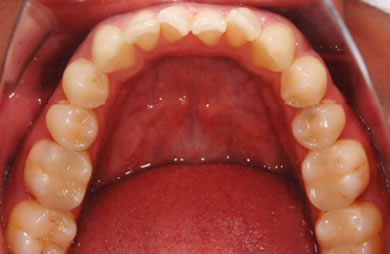

セラミックの症例写真 SHINBI

セラミック治療

| 性別/年齢 | 男性 / 29歳 | ||||||||||||||||||||||||||||||||

| 主訴 | 歯並びを綺麗にしたい。奥歯の銀歯が目立つので白くしたい。 | ||||||||||||||||||||||||||||||||

| 治療方針 | 上の前歯部に関しては審美的回復の優先を切望されているため、透明感のあるオールセラミックのハイクオリティタイプを使用。 | ||||||||||||||||||||||||||||||||

| 治療内容 | オールセラミック(ハイクオリティ)3本、ハイブリッドセラミックインレー10本 | ||||||||||||||||||||||||||||||||

| 総治療費 | 714,286円 | ||||||||||||||||||||||||||||||||

| 治療期間 | 7ヶ月 |